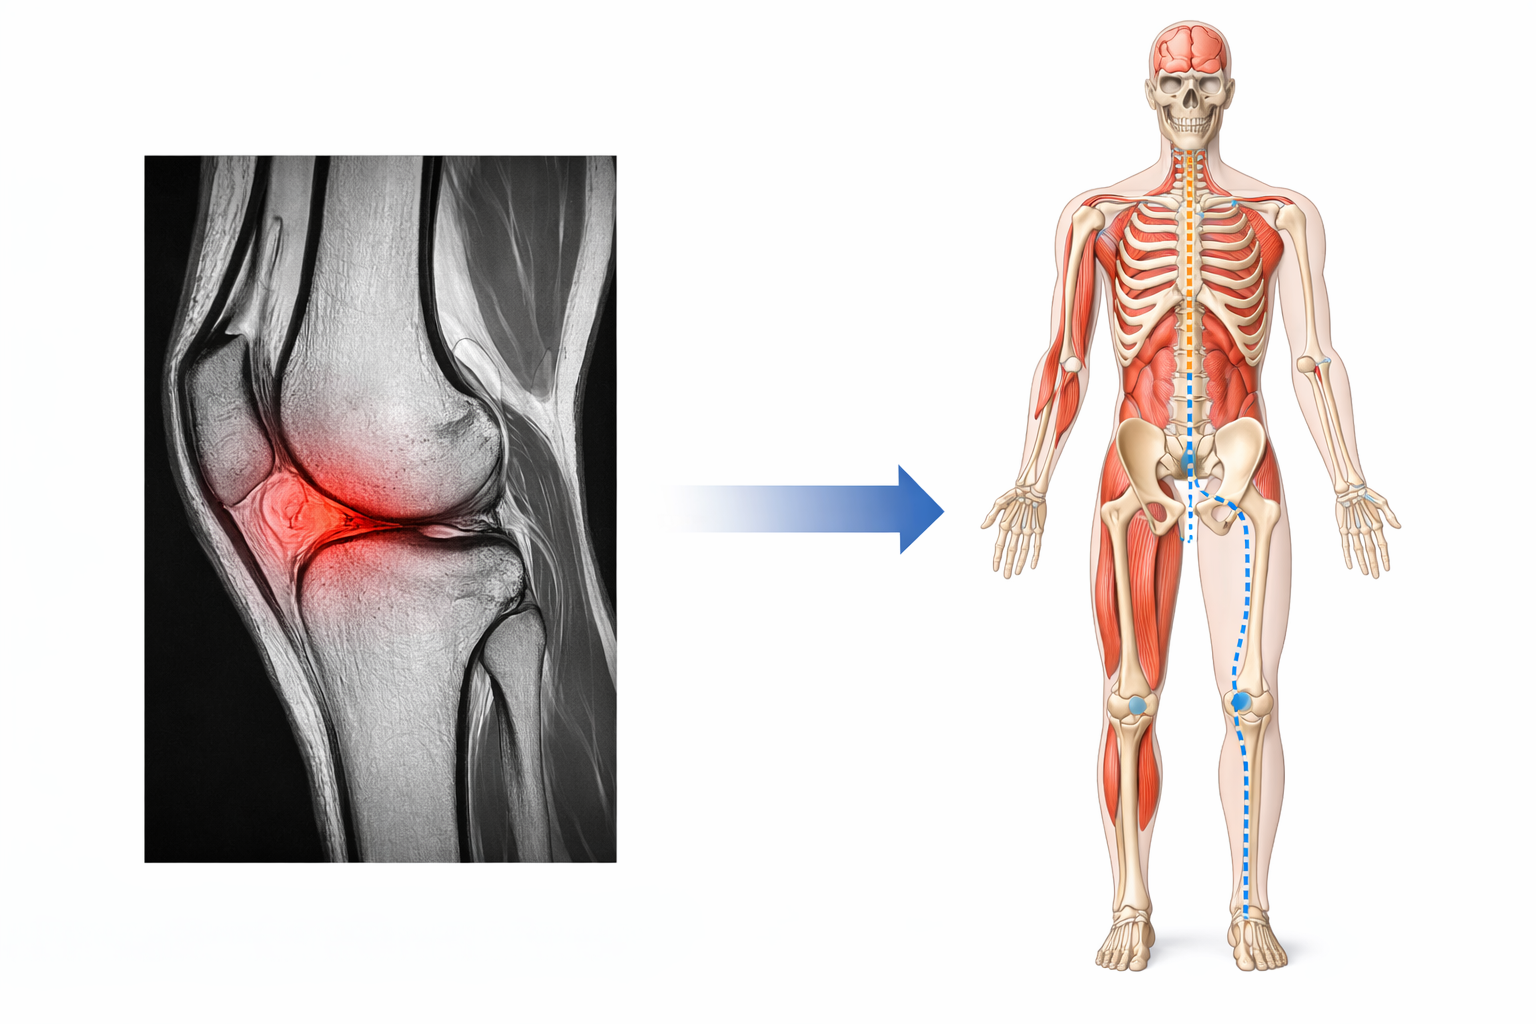

Knee Pain Is Often a Coordination Issue

The knee lives in the middle of a moving chain.

If motion is altered:

• In the hip

• In the pelvis

• In the low back

• Or in the way the nervous system coordinates movement

The knee often becomes the pressure point where stress shows up.

This is why two people with the same MRI findings can have completely different experiences:

• One feels fine

• The other struggles to walk

The difference is not the picture — it’s the organization of the system.

The nervous system coordinates the entire kinetic chain, linking the brain, spine, hips, knees, and feet into one adaptive system. When coordination or signal clarity is disrupted upstream, the knee often absorbs stress it was never designed to handle—resulting in pain without local damage.